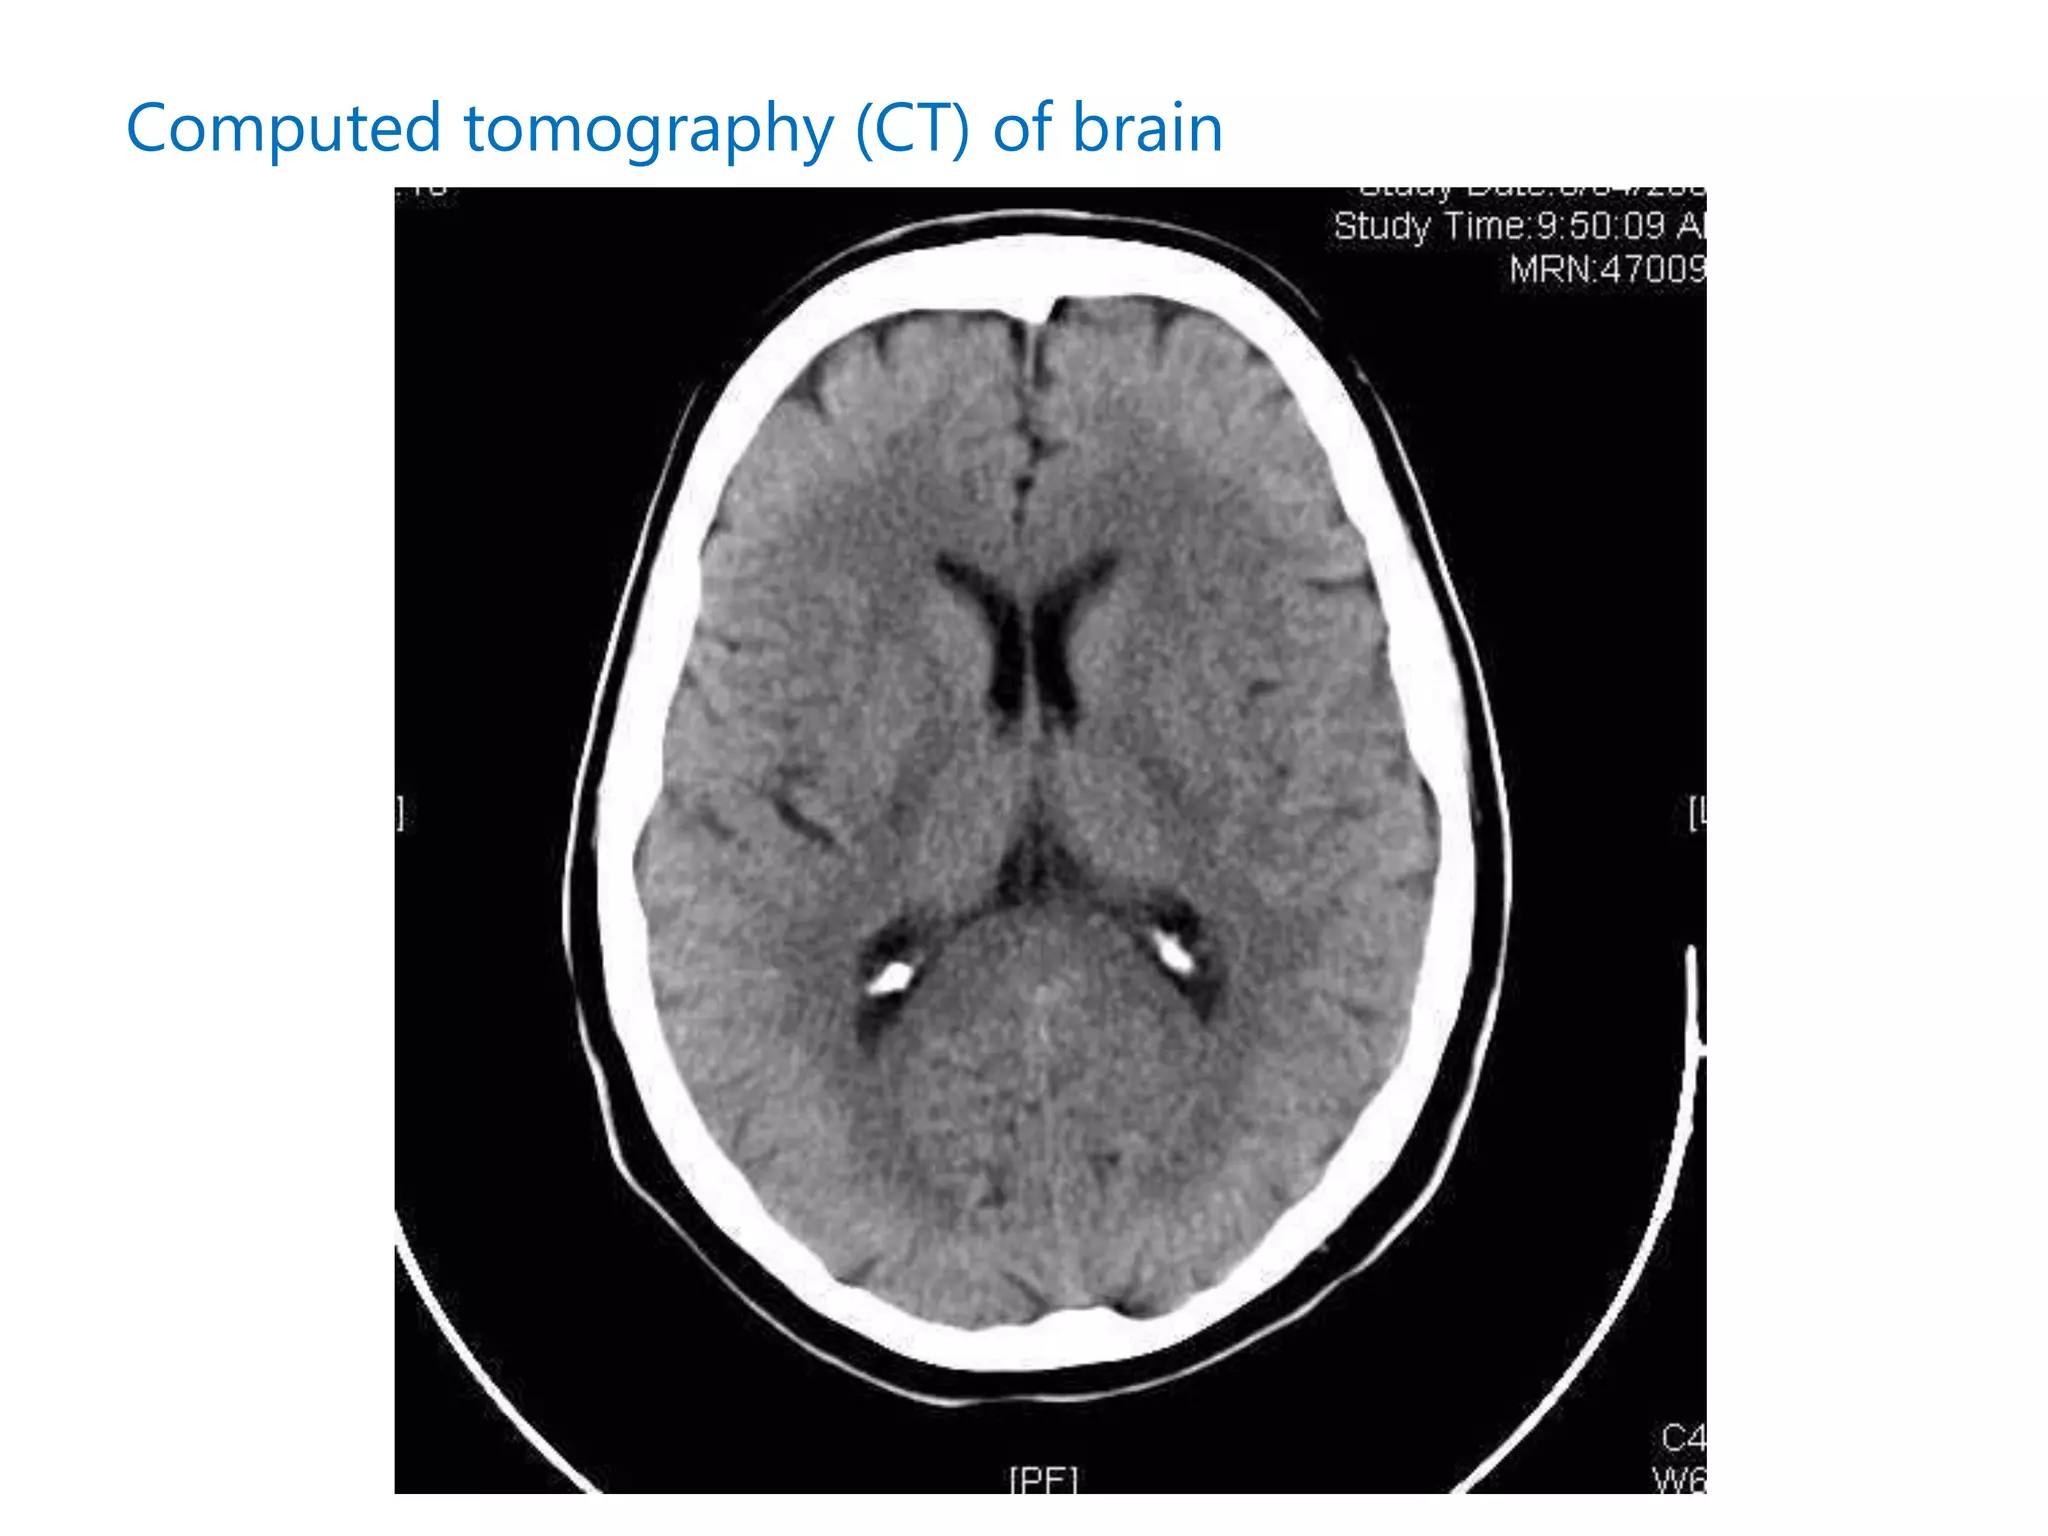

Computed tomography (CT) of brain

⑤ (意識障害、局所神経症状あれば) 頭部CT